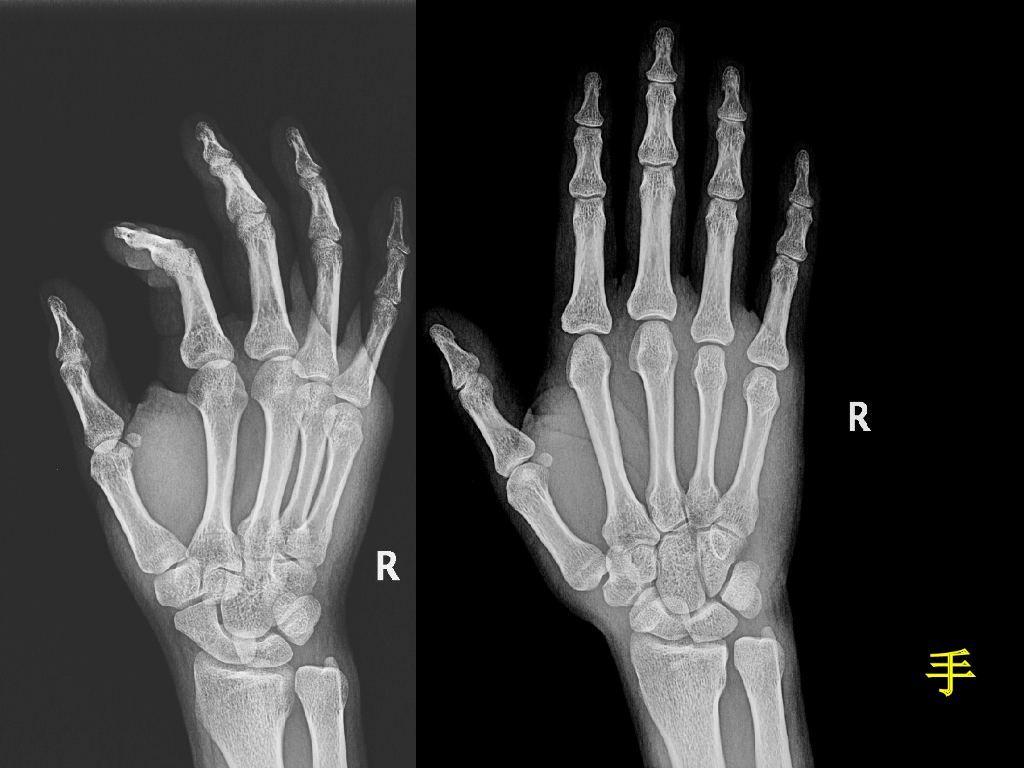

《放射诊断学》演示文稿-骨关节影像学检查与先天性畸形实习课.pdf